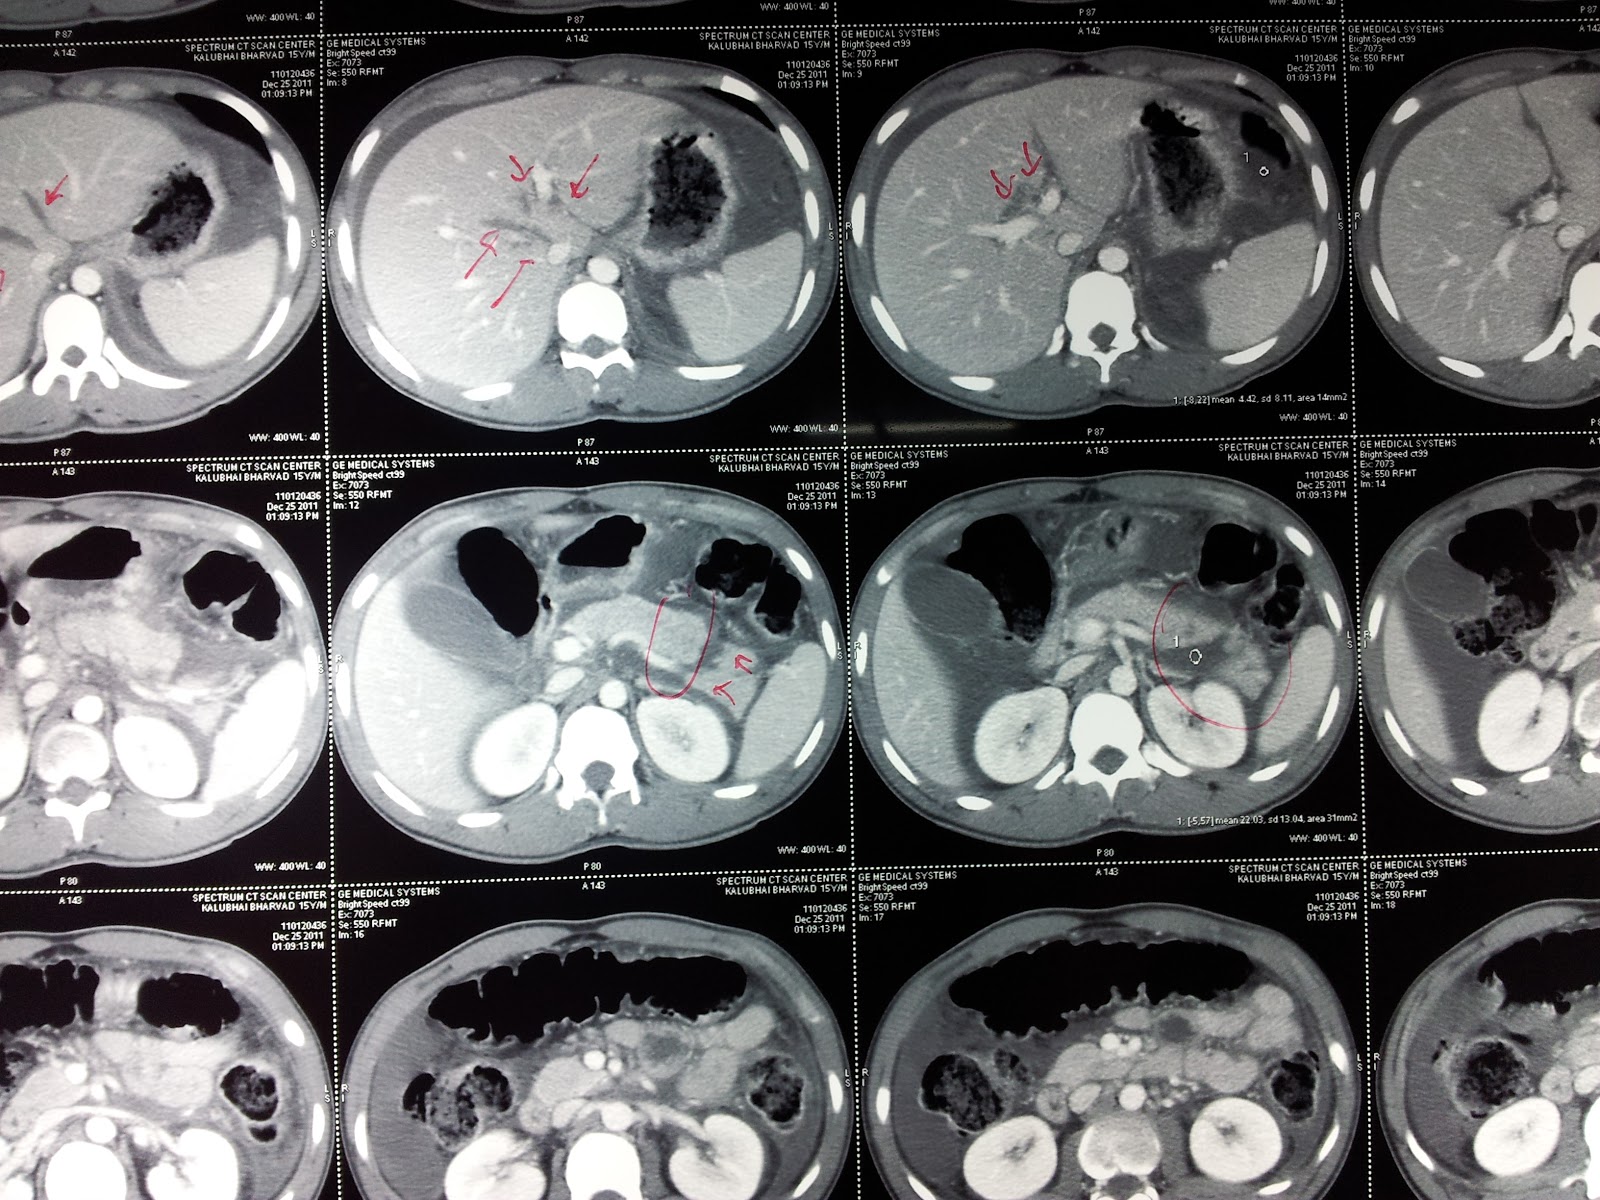

From drkeyurbhatt.blogspot.com

DR. KEYUR S. BHATT (MS, MRCSEd) CASE distal pancreatectomy with Ramps Distal Pancreatectomy Ramps procedure for lesions of the body and tail of the pancreas can retrieve significantly more lymph nodes than standard. In 2003, radical antegrade modular pancreato. In 2003, strasberg et al., from washington university, described a new distal pancreatectomy technique, termed ramps, to. Distal pancreatectomy is a common procedure for resectable distal pancreatic tumors. Radical antegrade modular pancreatosplenectomy (ramps) has. Ramps Distal Pancreatectomy.